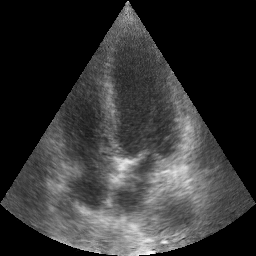

Transthoracic echo is one of the most common means of cardiac studies in the clinical routines. During the echo exam, the sonographer captures a set of standard cross sections (echo views) of the heart. Each 2D echo view cuts through the 3D cardiac geometry via a unique plane. Consequently, different views share some limited information. In this work, we investigate the feasibility of generating a 2D echo view using another view based on adversarial generative models. The objective optimized to train the view-conversion model is based on the ideas introduced by LSGAN, PatchGAN and Conditional GAN (cGAN). The size and length of the left ventricle in the generated target echo view is compared against that of the target ground-truth to assess the validity of the echo view conversion. Results show that there is a correlation of 0.50 between the LV areas and 0.49 between the LV lengths of the generated target frames and the real target frames.